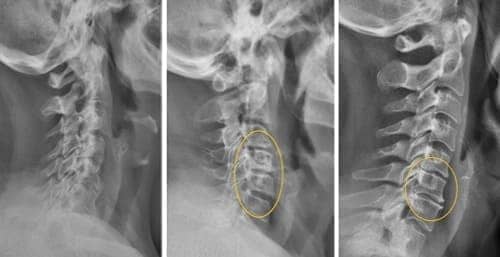

Hondro Sol hat eine vollständige Wiederherstellung der

Gelenkstruktur innerhalb von 1 Monat gezeigt (der niedrigste Prozentsatz war in der

Gruppe der Autoimmunerkrankungen und betrug 87% Wiederherstellung).

Hondro Sol ist bei der Behandlung von

Gelenken und der Wiederherstellung von Gelenkgeweben zehnmal wirksamer als herkömmliche

Arzneimittel.